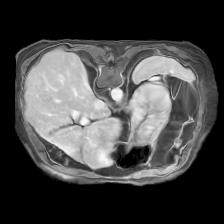

In clinical practice, well-aligned multi-modal images, such as Magnetic Resonance (MR) and Computed Tomography (CT), together can provide complementary information for image-guided therapies. Multi-modal image registration is essential for the accurate alignment of these multi-modal images. However, it remains a very challenging task due to complicated and unknown spatial correspondence between different modalities. In this paper, we propose a novel translation-based unsupervised deformable image registration approach to convert the multi-modal registration problem to a mono-modal one. Specifically, our approach incorporates a discriminator-free translation network to facilitate the training of the registration network and a patchwise contrastive loss to encourage the translation network to preserve object shapes. Furthermore, we propose to replace an adversarial loss, that is widely used in previous multi-modal image registration methods, with a pixel loss in order to integrate the output of translation into the target modality. This leads to an unsupervised method requiring no ground-truth deformation or pairs of aligned images for training. We evaluate four variants of our approach on the public Learn2Reg 2021 datasets \cite{hering2021learn2reg}. The experimental results demonstrate that the proposed architecture achieves state-of-the-art performance. Our code is available at https://github.com/heyblackC/DFMIR.